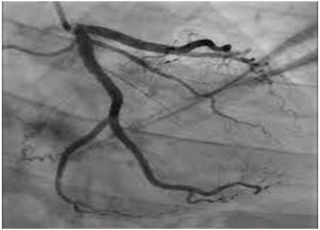

Coronary Angiography

An invasive procedure to look at heart arteries to investigate and potentially treat coronary heart disease with stents.